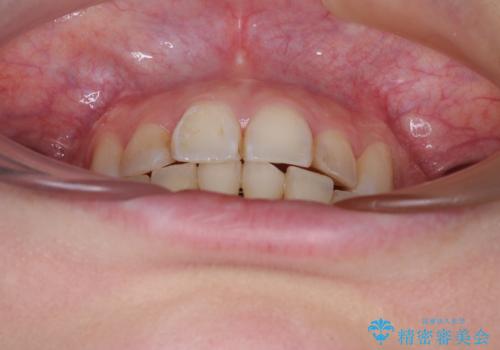

- 前歯のデコボコを気にして来院された患者様です。

上下の前歯にデコボコがあり、更にはディープバイトにより下顎前歯の大半が隠れている状態でした。